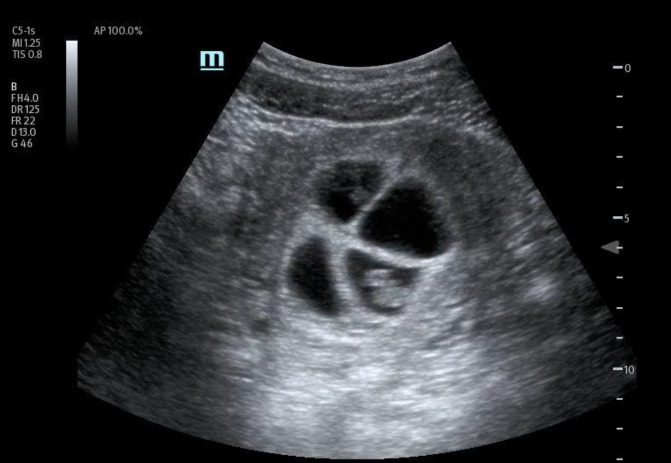

处理多胎妊娠具有挑战性,需要仔细评估。护理点超声检查(POCUS)已成为评估疑似头胎妊娠的潜在重要工具。然而,它在评估多胎妊娠中的作用仍不确定。我们介绍了一例 36 岁加纳女性的病例,她在接受体外受精后出现急性阴道出血。床旁经腹 POCUS 检查发现有四个宫内妊娠,胎儿有胎儿极和心脏活动,提示为四胞胎可存活妊娠。随后的经阴道超声检查证实了这一结果。患者出院后与妇产科医生进行了复诊。本病例强调了 POCUS 在早孕诊断中的重要性,有助于准确识别和适当转诊,以便进一步处理。它还证明了 POCUS 在确定孕龄和胎儿存活率方面的实用性。据我们所知,目前还没有发表过专门针对四胞胎妊娠诊断的病例报告,这强调了 POCUS 在优化高危多胎妊娠护理中的作用。

Managing multiple pregnancies is challenging and requires careful evaluation. Point of care ultrasound (POCUS) has emerged as a potentially crucial tool in assessing suspected first-trimester pregnancies. However, its role in evaluating multiple pregnancies remains uncertain. We present the case of a 36-year-old Ghanaian female who presented with acute vaginal bleeding after undergoing in vitro fertilization. A bedside transabdominal POCUS identified four intrauterine gestations with fetal poles and cardiac activity, suggesting a quadruplet viable pregnancy. A subsequent transvaginal ultrasound confirmed the findings. The patient was discharged with a follow-up appointment with an Obstetrician-Gynecologist. This case highlights the significance of POCUS in early pregnancy diagnosis, facilitating accurate identification and appropriate referral for further management. It also demonstrates the utility of POCUS in determining gestational age and viability. To our knowledge, no published case reports specifically address the diagnosis of a quadruplet pregnancy, emphasizing the role of POCUS in optimizing care for high-risk multiple pregnancies.